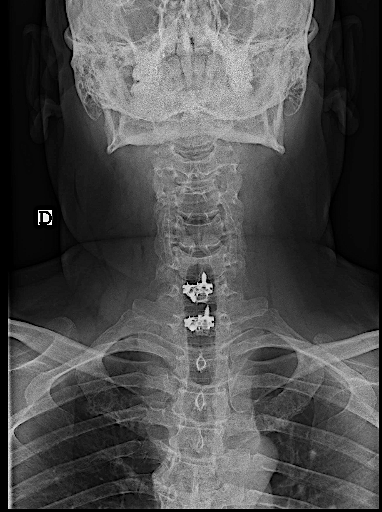

RX AP control postoperatoria.

Obsérvese, en la imagen anterior, la incisión usada en relación con la prótesis. No fue necesario realizar ninguna esternotomía (aunque el cirujano torácico estaba avisado). Para mejorar la visión sí que se resecó parte del platillo inferoanterior de Th1.

La caja atornillada no planteó tantas dificultades como la descompresión.

Difícilmente se aprecia la prótesis

Copia con marcaje de los tornillos de la misma

En las RX lateral de control no se aprecia bien la caja atornillada, sin embargo, la paciente mejoró la clínica álgica y mostró recuperación funcional en MSD en los controles, por lo que decidí esperar a los 6 meses para la RM cervical.